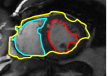

IV-A Tracking Multiple Regions

In cardiac image analysis, there are multiple structures (the right and left ventricles, and myocardium) that all useful and should be segmented. Our method is easily adaptable to this case. Indeed, computation of in Section III-C can be readily generalized. In general, multiple level sets should be used to represent multiple regions. However, in our case of interest (ventricles and surrounding epicardium), the regions form a rather simple topology (see Figure 3), and all regions can be represented using a single level set.

While theoretically for each will be an invertible/onto map in each individual region, and thus regions cannot change topology, numerically, between close by structures, merging/splitting may occur. Since we know that, in our application of interest, there is no such topology change, we enforce a hard topology constraint, that topology must not change during the level set evolution. This is now standard with level sets using discrete topology preserving techniques [14]. The original level set evolution is augmented with a step that looks for non-simple points that change sign in a level set update, i.e., locations of topology change. Such points are not allowed to change sign, and this preserves topology. Non-simple points are easily detected with local pixel-wise operations, and this makes implementation easy and the technique adds very little computational cost. The reader is referred to [14] for details on the criteria for simple points.